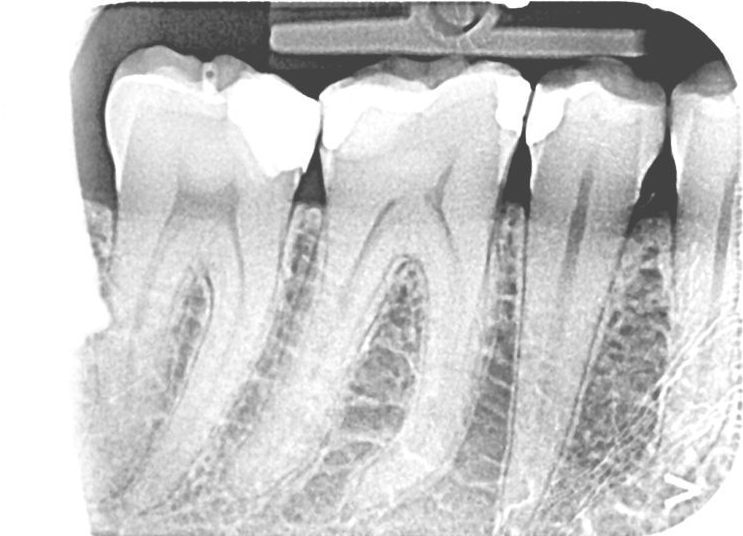

Vorig jaar heb ik een diepe vulling gekregen voor een van mijn kiezen. Na 10 dagen hevige pijn, is deze weggetrokken en is de situatie genormaliseerd. 1 jaar later heb ik nu een lastig gevoel aan deze tand. Ik ben net naar de tandarts geweest en die ziet niets op de foto, zie bijlage. De tand deed ook geen pijn toen hij er tegen tikte. Enkel koude was zeer gevoelig en pijnlijk, maar die pijn trok direct weg. Het gevoel blijft echter aanhouden. Bij het poetsen is de tand bij momenten ook gevoelig.

Ik zou nog een extra x-foto v d wortelpunt v d achterste kies willen zien. Mogelijk afwijking ontstaan door het afsterven v d zenuw. Indien zo een wortelkanaal behandeling laten uitvoeren. Is dat ook de kies waar u last v heeft...???..dan wkb. Een na achterste kies heeft een :diepe" vulling" waardoor de zenuw is teruggetrokken, zenuwkamer lijkt gecalcificeerd. Mogelijk is deze zenuw afgestorven. Vitaliteit testen..

Als u koude in de tand en niet het weefsel eromheen voelt betekent dat, dat de zenuw nog leeft en waarschijnlijk nog geen wkb nodig heeft. Toen dat getest werd herkende u het plaats delict?? oftewel dat is de kies waar ik ongemak v heb. Want het ongemak kan ook uitstralen v d achterste kies...daarom zou ik een tweede foto willen en dat element ook testen. Wil niet negatief zijn maar ik opperde de mogelijkheid dat mogelijk een v d 3/4 kanalen afgestorven is en ongemak veroorzaakt terwijl u toch koude ervaart door de nog levende kanalen. Tja dat is dan heel moeilijk. Als u de kies die op koude reageert ook herkent als de plaats delict, zou ik bij aanhoudende klachten toch een wkb doen.